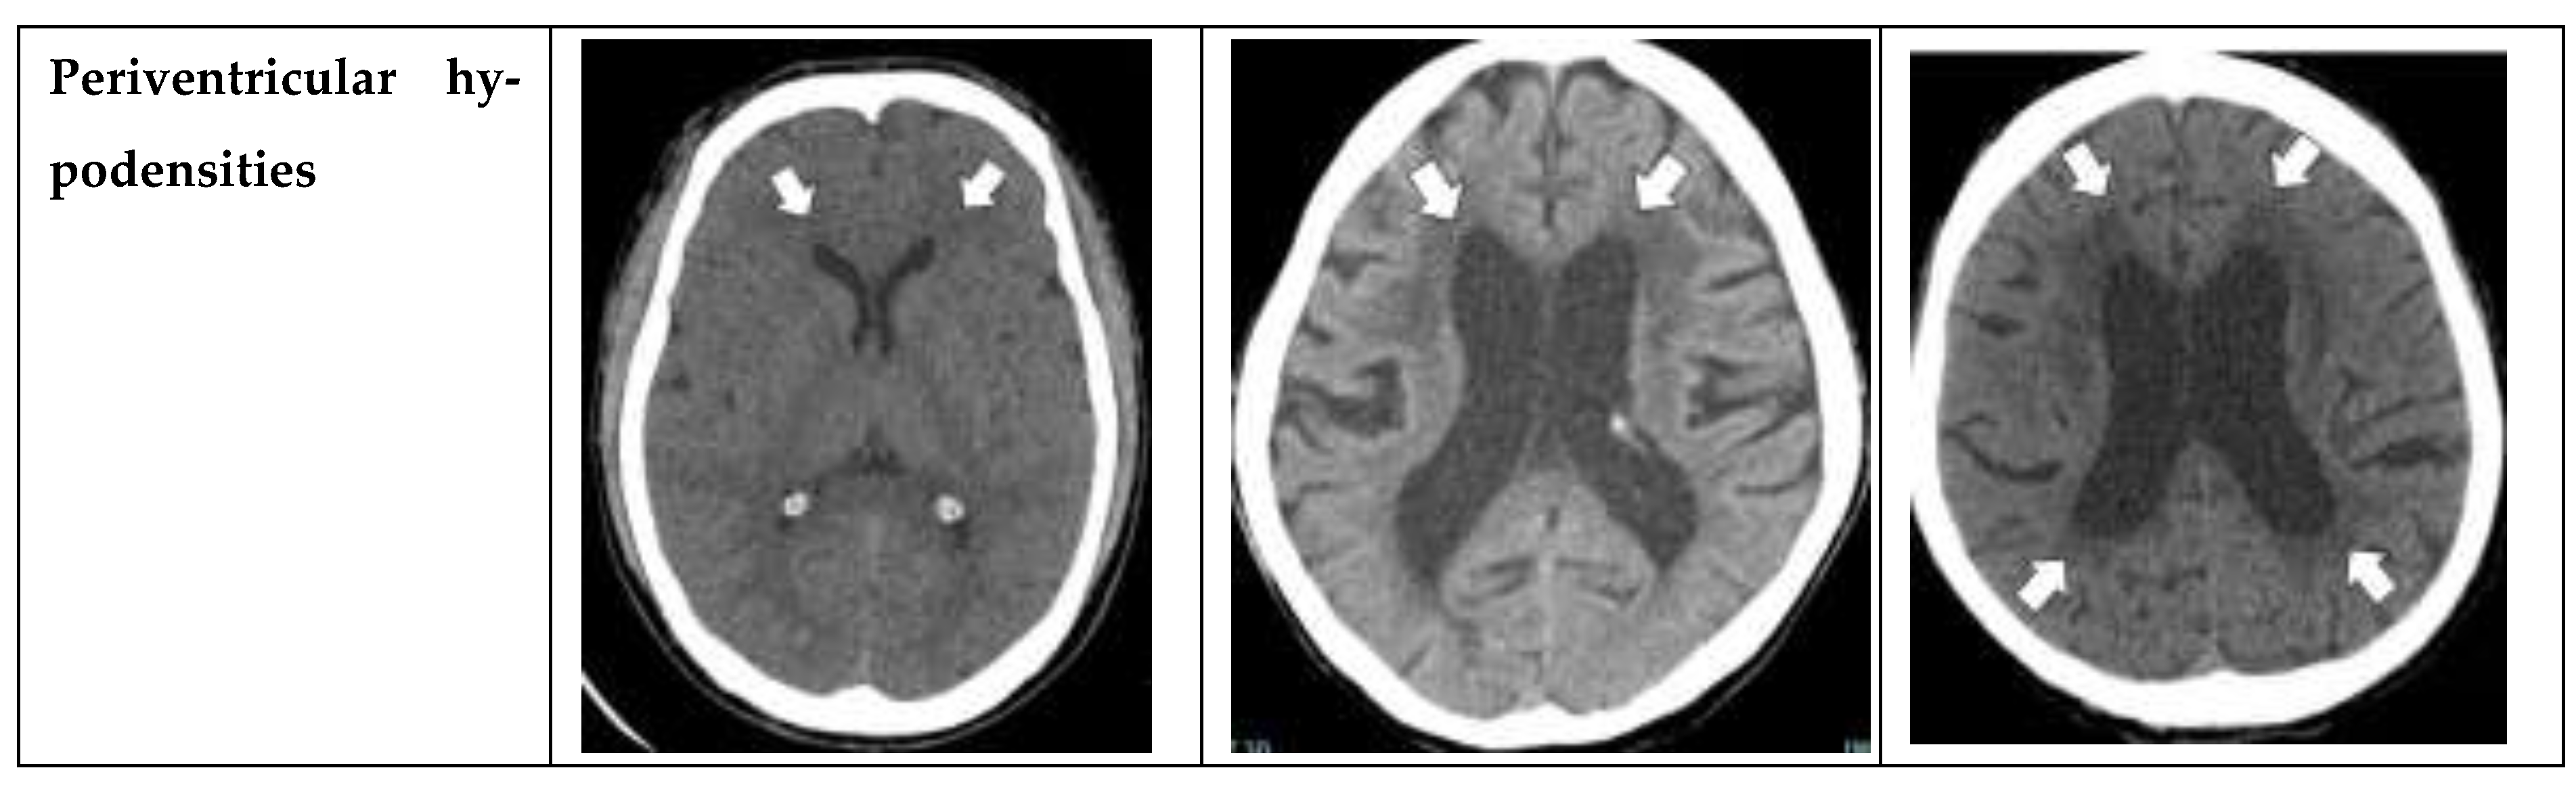

Seven radiological parameters were used in this study, including Evans’ index, narrow sulci at high parietal convexity, dilatation of the Sylvian fissures, focally enlarged sulci, widening of temporal horns, callosal angle, and periventricular hypodensities. Each radiological parameter was separately converted into a point system with cut-off values based on earlier studies [3] and total scores were calculated, ranging from 0 to 12 points. The study also compared the reliability of each imaging feature alone with that of the overall iNPH Radscale score. To standardize measurements of each radiologic parameters, the planes were carefully aligned with anatomical landmarks in both axial and coronal planes. The axial plane was positioned parallel to the pituitary-fastigium (of the fourth ventricle) axis, while the coronal plane was angulated perpendicular to the transverse plane for all measurements except for the callosal angle, which required a coronal plane perpendicular to the in-tercommissural plane [3].

• Periventricular hypodensities: along the lateral ventricles graded as not present, present as a cap around frontal horns or confluently extending around the lateral ventricles [10].